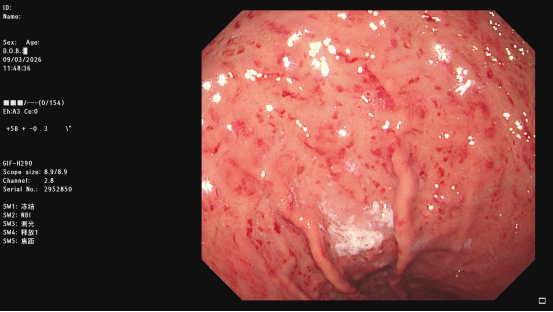

糜烂性胃炎是胃粘膜表层细胞受损导致的炎症,主要表现为胃粘膜出现点状、片状糜烂或渗血。可引发上腹痛、恶心、呕吐、食欲减退等症状。